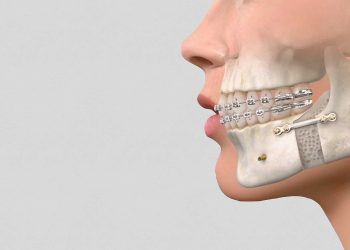

Ver mais...Procedimento corrige problemas funcionais, mas também está relacionada a uma melhoria na estética facial dos pacientes. A cirurgia ortognática tem...